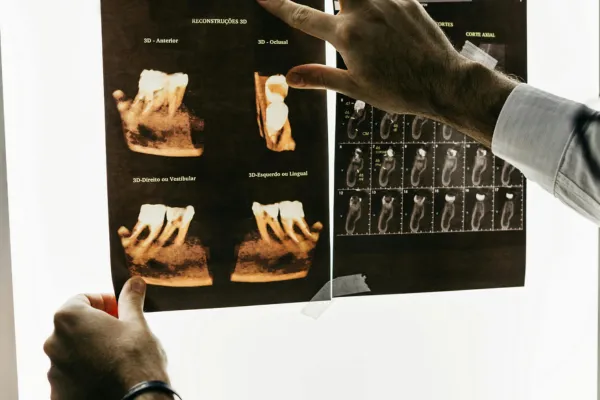

Dental X-Rays

Get accurate diagnosis with advanced dental X-rays in Islamabad. We use modern low-radiation digital imaging to detect cavities, infections, and hidden dental issues. This technology helps us create precise and effective treatment plans.